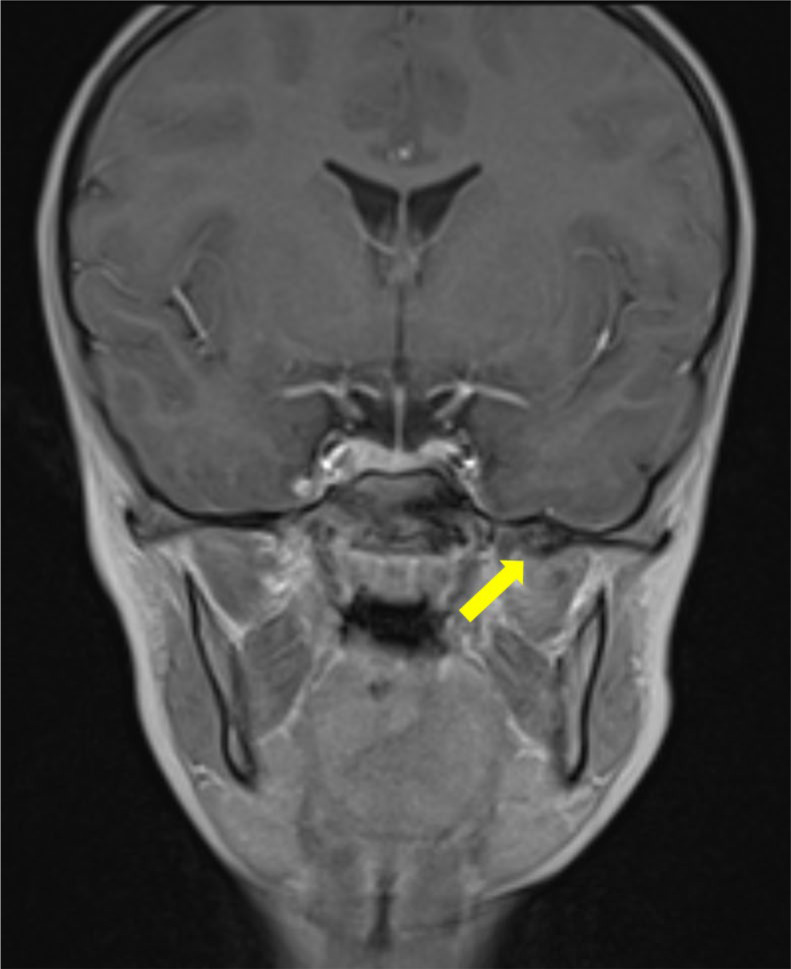

本报告报告一例非常罕见的8岁儿童,由蝶下颌韧带钙化引起的进行性限制开口(牙关)。这个病例突出了与这种疾病相关的诊断和治疗挑战的困难。我们讨论了详细的临床和放射学方法,包括用于识别钙化的成像技术,以及所选择的治疗方案,即颌面物理治疗。本报告提供了新的信息,现有文献对这种罕见的实体和提供有用的信息,临床管理类似的情况下。教学要点:蝶下颌韧带骨化症是一种非常罕见的导致张嘴受限的原因,也是一种具有挑战性的诊断。

This report aims to present a very rare case of progressive limited mouth opening (trismus) in an 8‑year‑old child caused by calcification of the sphenomandibular ligament. This case highlights the difficulty of diagnostic and therapeutic challenges associated with this disorder. We discuss the detailed clinical and radiological approach, including the imaging techniques used to identify the calcification, as well as the treatment option chosen, namely maxillofacial physiotherapy. This report provides new information to the existing literature on this rare entity and to provide useful information for the clinical management of similar cases. Teaching point: Sphenomandibular ligament ossification is a very rare cause of limitation of mouth opening and can be a challenging diagnosis.